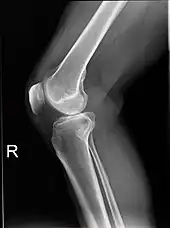

Projectional radiographs

Projectional radiography is the practice of producing two-dimensional images using X-ray radiation. Bones contain a high concentration of calcium, which, due to its relatively high atomic number, absorbs X-rays efficiently. This reduces the amount of X-rays reaching the detector in the shadow of the bones, making them clearly visible on the radiograph. The lungs and trapped gas also show up clearly because of lower absorption compared to tissue, while differences between tissue types are harder to see.[113]

Projectional radiographs are useful in the detection of pathology of the skeletal system as well as for detecting some disease processes in soft tissue. Some notable examples are the very common chest X-ray, which can be used to identify lung diseases such as pneumonia, lung cancer, or pulmonary edema, and the abdominal x-ray, which can detect bowel (or intestinal) obstruction, free air (from visceral perforations), and free fluid (in ascites). X-rays may also be used to detect pathology such as gallstones (which are rarely radiopaque) or kidney stones which are often (but not always) visible. Traditional plain X-rays are less useful in the imaging of soft tissues such as the brain or muscle. One area where projectional radiographs are used extensively is in evaluating how an orthopedic implant, such as a knee, hip or shoulder replacement, is situated in the body with respect to the surrounding bone. This can be assessed in two dimensions from plain radiographs, or it can be assessed in three dimensions if a technique called '2D to 3D registration' is used. This technique purportedly negates projection errors associated with evaluating implant position from plain radiographs.[114]